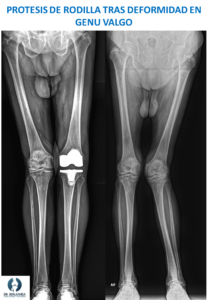

Lo habitual es que el traumatólogo indique realizar radiografías de la rodilla para valorar el grado de artrosis, lo que junto a lo que nos cuenta el paciente y la exploración física determinan la indicación de la prótesis. En ocasiones una resonancia magnética también puede darnos datos sobre el estado del cartílago de la rodilla.

La cirugía de prótesis de cadera es un procedimiento estandarizado, que se realiza siguiendo pasos muy concretos. La cirugía suele hacerse bajo anestesia general o raquídea (parecida a la epidural), y la intervención completa dura entre 1 y 2 horas.  La prótesis se coloca con un abordaje anterior, es decir a través de una incisión delante de la rodilla. Tras retirar el tejido articular dañado mediante unos cortes en el hueso, se colocan los implantes de prueba y comprobamos la movilidad y la estabilidad de la nueva rodilla. Si estamos conformes con las pruebas pasamos a colocar los implantes definitivos. Gracias al avance en la técnica quirúrgica y los nuevos instrumentales, el sangrado intraoperatorio cada vez es menor por lo que es raro necesitar una transfusión sanguínea.